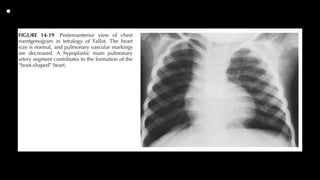

• Radiography

Cyanotic Tetralogy of Fallot

1. The heart size is normal or smaller than normal, and

pulmonary vascular markings are

decreased. “Black” lung fields are seen in TOF with pulmonary

atresia.

2. A concave main PA segment with an upturned apex (i.e., “boot-

shaped” heart or coeuren sabot) is characteristic (Fig. 14-19).

3. RA enlargement (25%) and right aortic arch (25%) may be

present.

Acyanotic Tetralogy of Fallot

Radiographic findings of acyanotic TOF are indistinguishable from

those of a small to moderate VSD (but patients with TOF have

RVH rather than LVH on the ECG).

• Tetralogy of Fallot and

tracheoesophageal

fistula

Neonate with "boot-shaped"

heart consistent with

subsequently proven tetralogy

of Fallot.

Nasogastric tube is coiled in

proximal esophagus,

transparency of esophagus is

interrupted on lateral view, and

distal esophagus apparently

connected to trachea by

continuous lucency that

represents tracheoesophageal

fistula.